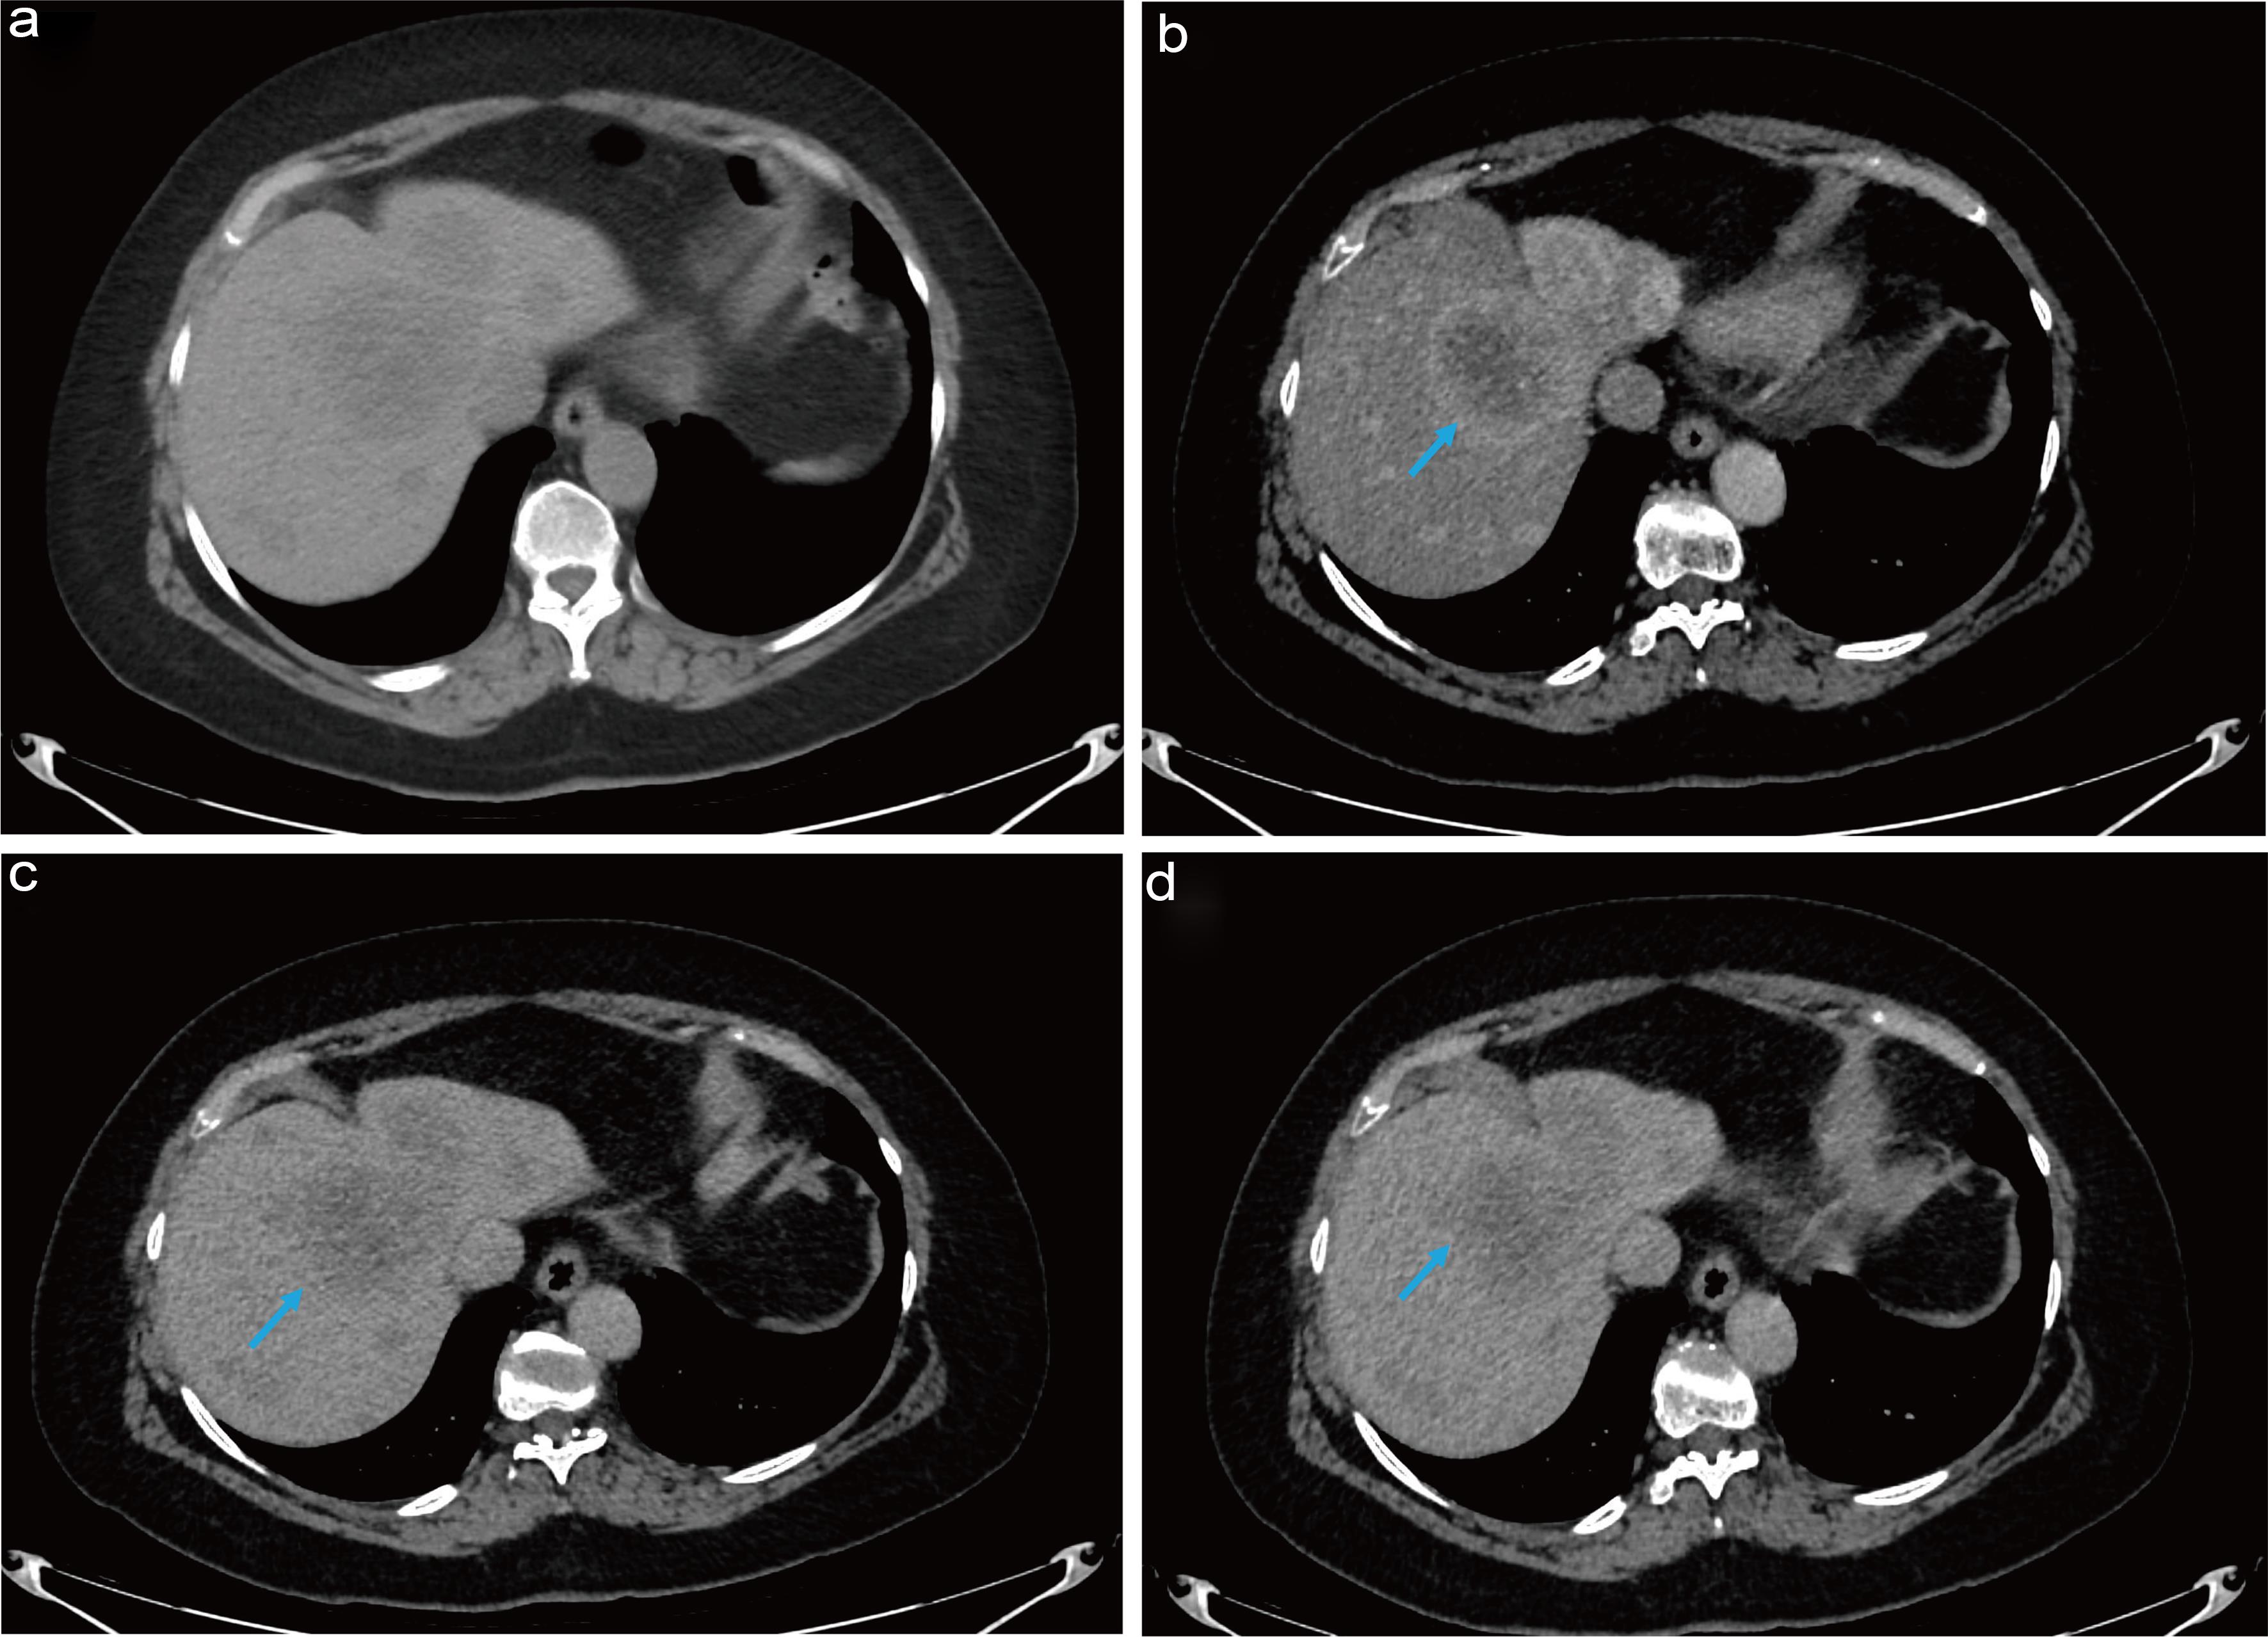

These findings, combined with normal IGF-2 levels, indicated that the hypoglycemia was due to hyperinsulinemia rather than an IGF-2-mediated process. Initial CT imaging revealed multiple masses throughout both lobes of the liver, with the largest lesion centrally located in the right lobe, measuring approximately 6.2 cm. There was peripheral enhancement and central hypoenhancement that persisted on both early and delayed post-contrast images. This pattern is not entirely typical of any benign etiology. HCC appears on CT as a mass that enhances during the arterial phase and washes out in the portal or delayed venous phase.5 However, because the patient did not have underlying cirrhosis or hepatitis, the Liver Imaging Reporting and Data System criteria could not be reliably applied.6 Consequently, previous scans were reviewed, and a triphasic CT scan of the liver was performed. This subsequent scan demonstrated an interval increase in lesion size, another feature favoring HCC (Fig. 2).

Subsequent CT scan (a) contrast enhanced- arterial phase, (b) portal venous phase, PET scan (c) DOTATATE avid pancreatic lesion, (d) DOTATATE avid liver metastases.

Fig. 2  Subsequent CT scan (a) contrast enhanced- arterial phase, (b) portal venous phase, PET scan (c) DOTATATE avid pancreatic lesion, (d) DOTATATE avid liver metastases.

CT, computed tomography; PET, positron emission tomography.

The scan also identified a sub-centimeter hypodense lesion with calcifications in the pancreatic tail. Given the suspicion of insulinoma, an esophagogastroduodenoscopy with endoscopic ultrasound and magnetic resonance cholangiopancreatography were performed but showed no definitive evidence of a pancreatic lesion. Consequently, a positron emission tomography DOTATATE (PET-DOTATATE) scan was scheduled to evaluate for a neuroendocrine tumor (NET). The result revealed intense somatostatin receptor-positive bilobar liver lesions, consistent with malignancy, as well as intense tracer avidity in the gastro-pancreatic region, likely misregistered from the pancreatic tail (Fig. 2). This finding raised suspicion for a primary neuroendocrine neoplasm, correlating with the calcification previously noted on CT.